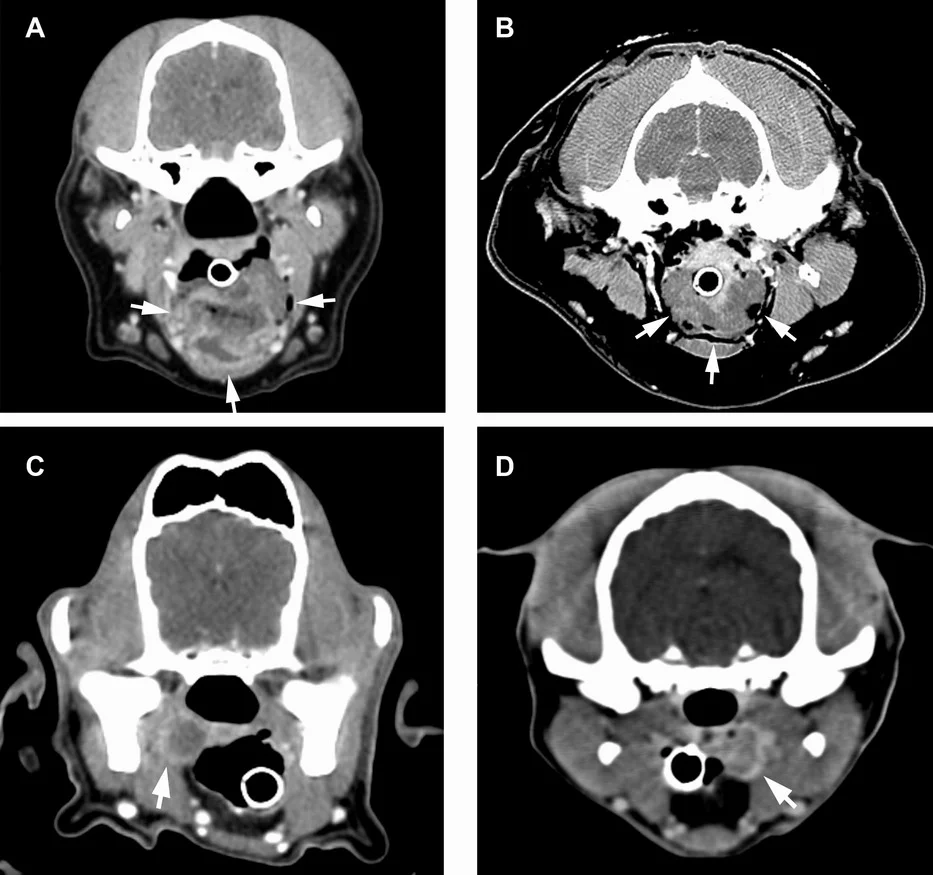

CT (počítačová tomografie)

CT vytváří detailní „řezové“ snímky hlavy a dokáže rozlišit kosti, měkké tkáně i dutiny. Hodí se pro širokou škálu vyšetření, například:

- úrazy lebky, zlomeniny a deformace kostí,

- nádory a útvary v oblasti hlavy,

- onemocnění dutiny nosní a vedlejších nosních dutin (záněty, polypy, nádory),

- onemocnění středního a vnitřního ucha,

- změny na zubech a čelisti (zubní abscesy, záněty, cysty),

- krvácení nebo jiné poruchy v mozku,

- vrozené vady lebky a mozkových struktur.

CT je rychlé a přesné, ale vyžaduje anestezii či sedaci, aby se zvíře nehýbalo.